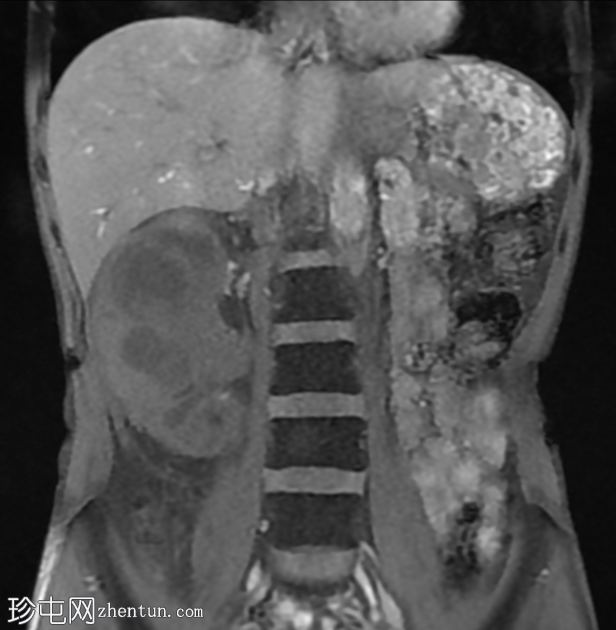

MRI

冠状位T1加权像

脂肪抑制序列

冠状位T2加权像

再次观察到上述肾前部外生性病变,其实性成分在T1加权像上呈等高信号,在T2加权像上呈低信号,伴有碎片扩散受限和低ADC值(化脓性物质)。囊性成分内部可见液-碎片/脓液界面。可见内部低信号结石。可见肾周模糊影。该病变压迫并可能侵犯右肾盂,导致中度肾积水。

病灶不规则的低信号,以及液-液界面伴有碎屑(可能为化脓性物质)扩散受限和肾周模糊,再次高度提示炎症性病变(黄色肉芽肿性肾盂肾炎,XGP),而非可能性较小的肿瘤。

左肾萎缩,体积较小,内含多发低信号结石。